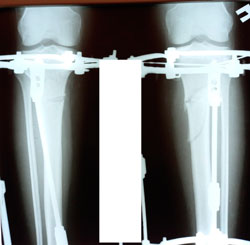

Исходник - 33 года.

Дата операции - 25.01.2021